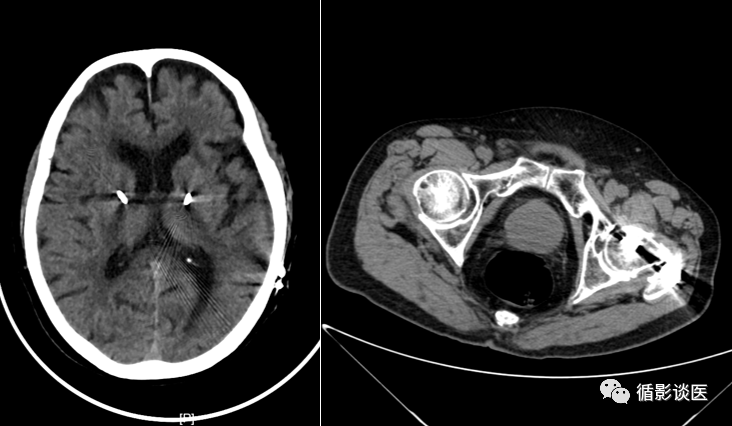

如图:如果金属物在我们所需要观察的器官内,效果如图,就会影响影像显示。